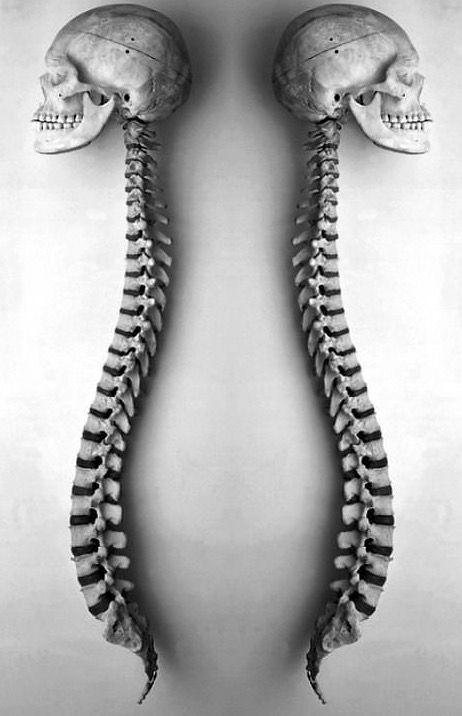

- 脊柱功能性疼痛是怎么回事?治疗方案是什么? 布骨康复医疗中心 ,2020-02-03

- 脊柱的最长部分,脊背主要负责保护脊髓。虽然它是由肋骨支撑的,但它仍然可能是疼痛和不适的部位。在电脑前工作常常是问题的原因! 背或胸椎有12节椎骨,从最后一节颈椎到第一节腰椎,呈自然弯曲,称为后凸。它的作用是支撑身体和保护脊髓。肋骨与背脊骨相连。 .....

- 脊柱是我们身体的中心支柱,如果出现背痛,解决方案是什么? 布骨康复医疗中心 ,2020-02-02

- 脊柱,也被称为脊柱或脊椎骨,是我们身体的中心支柱。 它的主要作用之一是引导躯干允许我们做的许多动作:弯曲、伸展、旋转、倾斜。它由24个椎骨组成:7个颈椎骨,12个胸椎骨和5个腰椎椎骨,5个骶骨椎骨和3 - 5个尾骨椎骨。像所有的关节一样,椎骨是由许多韧带和肌肉连接在一起的。它们由一个椎间盘隔开,椎.....